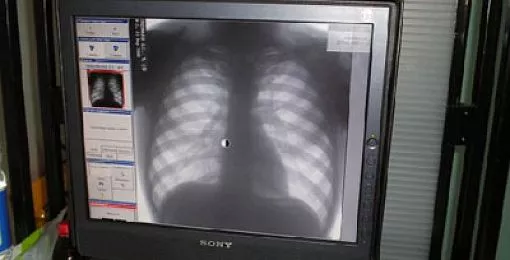

Регулярное флюорографическое обследование — надежная профилактика туберкулеза

Флюорография для взрослых и подростков, проведение туберкулинодиагностики у детей (реакция Манту) — это основные и самые доступные для всех методы ранней диагностики туберкулеза, что также является профилактикой, поскольку в случае выявления болезни прерывается «цепочка» распространения инфекции. Стремимся к 100-процентному обследованию групп риска, декретированного контингента (медики, педагоги, работники торговли, пищевики и т.д.) и лиц, не обследовавшихся 2 года и более (именно в этой группе выявляемость туберкулеза в три раза выше, чем среди остальных). Продолжаем работу с правоохранительными органами по привлечению туберкулезных больных, уклоняющихся от обследования и лечения.